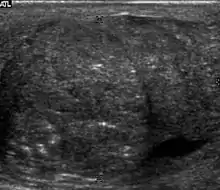

Embryonal cell carcinomas, a more aggressive tumor than seminoma usually occurs in men in their 30s. Although it is the second most common testicular tumor after seminoma, pure embryonal cell carcinoma is rare and constitutes only about 3 percent of the nonseminomatous germ cell tumors. Most of the cases occur in combination with other cell types. At ultrasound, embryonal cell carcinomas are predominantly hypoechoic lesions with ill-defined margins and an inhomogeneous echotexture. Echogenic foci due to hemorrhage, calcification, or fibrosis are commonly seen. Twenty percent of embryonal cell carcinomas have cystic components. The tumor may invade into the tunica albuginea resulting in contour distortion of the testis [Fig. 4].